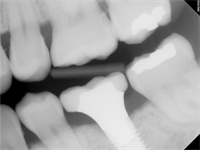

"Emergence Profile": or lack of one

This patient's chief complaint was the food impaction on the distal of #19. I could not help but notice the pancake sitting on top of the implant. I'll save the criticism because I don't know the details and circumstances surrounding this case. The radiograph beautifully illustrates the...  Read More